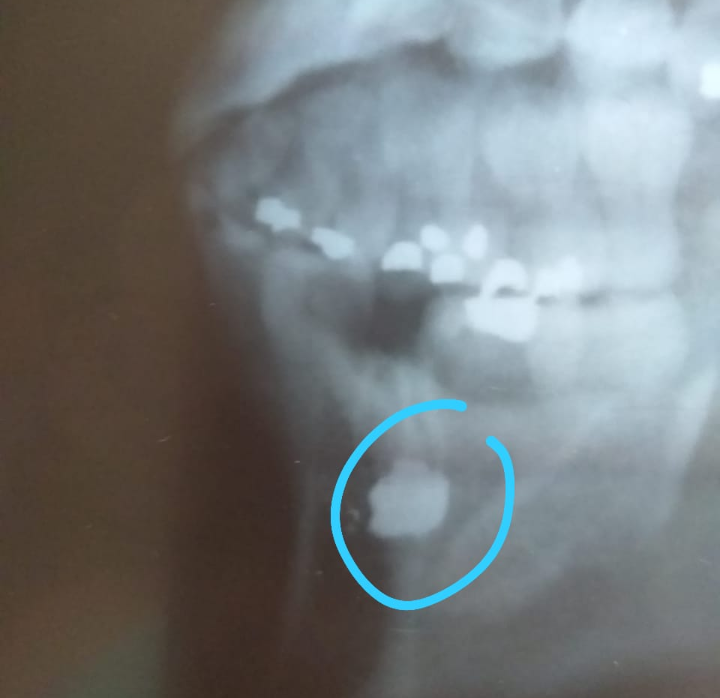

O fragmento do projétil furou a máscara que a GM usava e atingiu o queixo causando fissuras ósseas.

Após o impacto, quando retirou a máscara havia muito sangue e foi orientada a lavar o locar e colocar gelo, informaram que era apenas um arranhão, mas, continuou sangrando. A GM foi para o ônibus se deitou um pouco, mas, estava com dor de cabeça e o sangramento não passava, ela chegou a ser chamada a retornar às atividades e informou que não tinha mais condições de participar. Depois do término das aulas, a jovem guarda foi para casa, ao chegar em sua residência o local atingido já estava inchado, então foi para o hospital, atendido na UPA Estadual, lá foi transferida para o Hospital Geral Clerisston Andrade, fez exames e a retirada do fragmento.